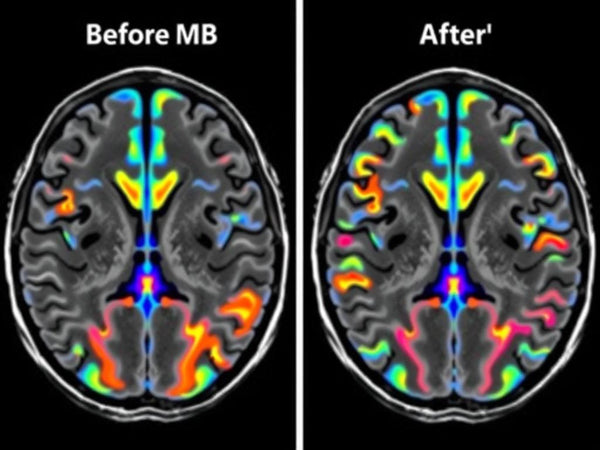

Brain activity comparison before and after methylene blue administration, showing increased activity in cognitive regions.

- Research in Radiology used functional MRI to demonstrate that methylene blue modulates brain network activity in humans, enhancing memory and attention.